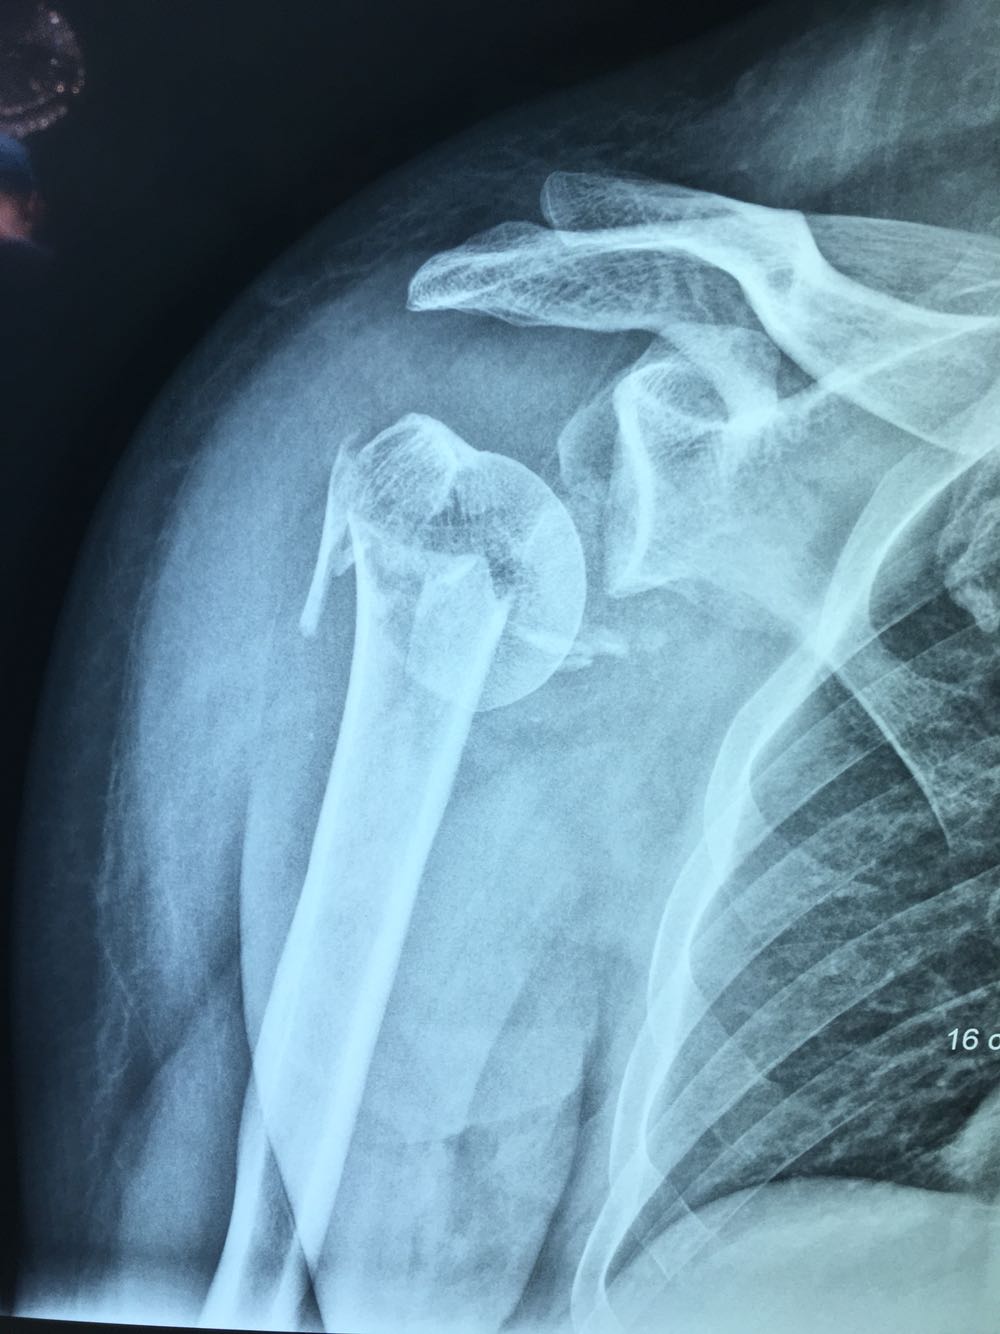

诊断:右肱骨近端骨折 治疗:臂丛备全麻下行右肱骨近端骨折切开复位内固定术,手术过程顺利,麻醉完全,骨折部位复位良好。

术前评估:ASA分级1级。患者术前中度贫血,手术部位出血量可能较大,术前备血红细胞2u,血浆200ml;手术部位较高,臂丛可能阻滞不全,随时准备插管全麻。